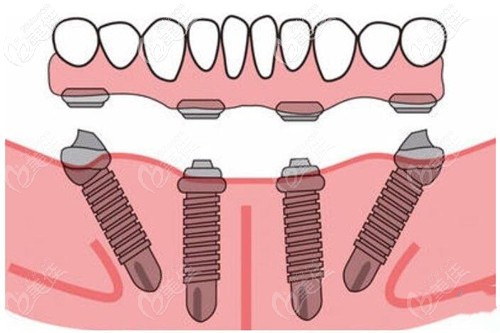

比較合適的方案就是做拔掉殘余的牙齒,上牙種植6顆、下牙種植6的全口即刻種植、即刻修復(fù)。可以避免植骨粉,還能當(dāng)天種牙后,就能戴牙冠,回家就能正常吃飯啊什么的。

因為也知道姥爺?shù)难例X情況,所以我就替他決定了做這個allon-6全口種植,選擇的是進(jìn)口的登騰種植體,一共十來萬吧,相對種植牙的價格來講,性價比高些。